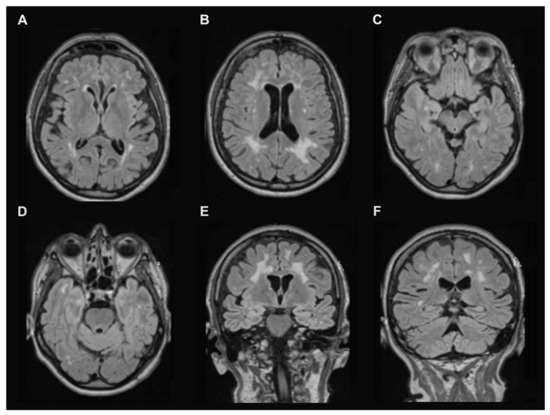

3.1. Brain MRI